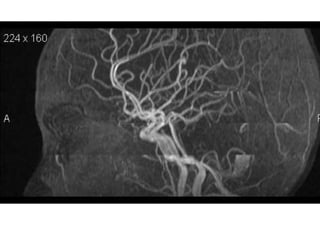

Arteries of the brain (lateral view) - MRA

1. Anterior cerebral artery

2. Anterior communicating artery

3. Basilar artery

4. branches (in insula) of middle cerebral artery

5. Cavernous portion of internal carotid artery

6. Cervical portion of internal carotid artery

7. Genu of middle cerebral artery

8. Intracranial (supraclinoid) internal carotid artery

9. Middle cerebral artery

10. Ophthalmic artery

11. Petrous portion of internal carotid artery

12. Posterior cerebral artery

13. Posterior cerebral artery in ambient cistern

14. posterior cerebral artery in interpeduncular

cistern

15. Posterior communicating artery

16. Posterior inf cerebellar artery.

17. Quadrigeminal portion of posterior cerebral

artery

18. Superior cerebellar artery

19. Vertebral artery